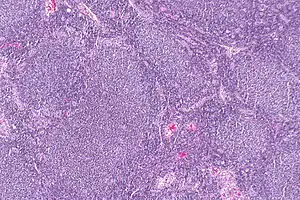

Follicular lymphoma (FL) is a cancer that involves certain types of white blood cells known as lymphocytes. The cancer originates from the uncontrolled division of specific types of B-cells known as centrocytes and centroblasts. These cells normally occupy the follicles (nodular swirls of various types of lymphocytes) in the germinal centers of lymphoid tissues such as lymph nodes. The cancerous cells in FL typically form follicular or follicle-like structures (see adjacent Figure) in the tissues they invade. These structures are usually the dominant histological feature of this cancer.[1]

| Micrograph of a follicular lymphoma, showing the characteristically abnormal lymphoid follicles that gave the condition its name. H&E stain. | |

The diagnosis of FL depends on examining involved tissues for histological, immunological, and chromosomal abnormalities that are indicative of the disease. FL usually involves enlarged lymph nodes populated by abnormal follicles (see adjacent picture) that when examined histologically contain a mixture of centrocytes or centroblast surrounded by non-malignant cells, mostly T-cells. The centrocytes, which typically outnumber centroblasts, are small to medium-sized B-cell lymphocytes that characteristically exhibit cleaved nuclei; the centropblasts are larger B-cell lymphocytes without cleaved nuclei.[11] Rare cases of FL may show lesions that contain tissue infiltrations dominated by B-cells with features of precursor (i.e. "blast") cells, monocytes, or malignant mantle cells such as those found in mantle cell lymphoma.[1] Immunochemical analyses reveal that these cells generally express B-cell surface markers including the CD10 (60% of cases), CD20, CD19, CD22, and CD79 but not CD5, CD11c, or CD23 cell surface proteins;[4] genomic analyses reveal that these cells contain t(14:18)(q32:q21.3) translocation (85–90% of cases), 1p36 deletions (60–70% of cases), and with far less frequency the other genomic abnormalities listed in the above sections on Pathophysiology and Presentation and course. None of these protein markers or genomic abnormalities are diagnostic for FL, e.g. the t(14:18)(q32:q21.3) translocation is found in 30% of diffuse large B-cell lymphoma and in a small number of reactive benign lymph nodes. Rather, the diagnosis is made by a combination of histological, immunological, and genomic abnormalities.[4] According to World Health Organization (WHO) criteria, follicular lymphoma can be classified morphologically by the relative amount of centroblasts. However, such classification is optional, due to poor reproducibility and little difference in prognosis and treatment, except that a lymphoma with almost only centroblasts may be diagnosed as a diffuse large B-cell lymphoma (DLBCL).[50] The optional classification of follicular lymphoma is as follows:[51]